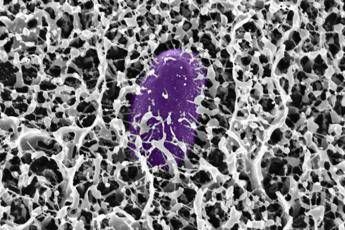

I ricercatori hanno scoperto che quando la Salmonella enterica viene esposta alla mucina MUC2, il batterio interrompe la produzione delle proteine codificate sull'”isola di patogenicità 1” (Salmonella pathogenicity island 1, SPI-1), essenziali per il sistema di secrezione di tipo 3 (T3SS) che permette al batterio di infettare le cellule ospite. Ulteriori analisi hanno rivelato che la MUC2 raggiunge questo risultato disattivando una proteina batterica di regolazione cruciale, nota come HilD. Bloccando questa proteina, la mucina impedisce l'attivazione dei geni T3SS. Utilizzando simulazioni computazionali, è stato dimostrato che alcuni monosaccaridi, come GlcNAc e GalNAc, possono legarsi al sito attivo della proteina HilD. Tuttavia, lo spegnimento dei geni avviene solo quando questi glicani sono ancorati alla spina dorsale peptidica della mucina. Lo studio ha inoltre rivelato che una mucina simile, la MUC5AC, presente nello stomaco, condivide questa capacità. I ricercatori dell'MIT, guidati da Katharina Ribbeck, Andrew and Erna Viterbi Professor of Biological Engineering e autrice senior dello studio, intendono ora esplorare l'uso di versioni sintetiche di queste molecole per potenziare le difese naturali del tratto gastrointestinale.